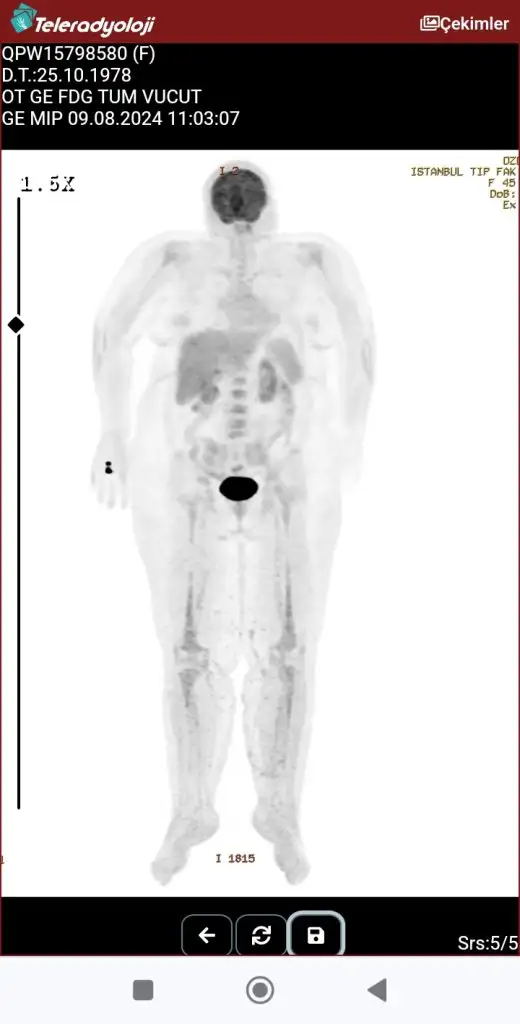

Merhaba arkadaşlar bugün pet filmi çekildi annem sonuçlar 15 gün sonra çıkacak merak ettiğim için buraya Konu açmak istedim sadece görüntü var elimde bu görüntünden bir şey anlaşılır mı anlayanlar yazabilir mi

İlacın tutulum yaptığı bi yer var gibi görünmüyor ama raporsuz çok da anlaşılmaz tabii en azından bizler için

İlaç tutulum yaptığında nasılbelli oluyor diğer hareketli görüntülerde var anlayan varsa atabilirim

Ben sağlıkçı değilim annem çok sık pet çektirdiği için görüntülere aşinayım sadece, yumurtalıklarında büyük bi kitle var mesela renkli olan görüntüde renkleri böyle görünüyor.

Geçen gün arkadaşımın annesi de pet çekindi o da bana attı merak ettiği için ama onda rapor da vardı, görüntü sizin gibiydi ve hiç tutulum göstermemişti doktorlar da sorun görmemişlerdi. Umarım sizde de öyle çıkar çok geçmiş olsun